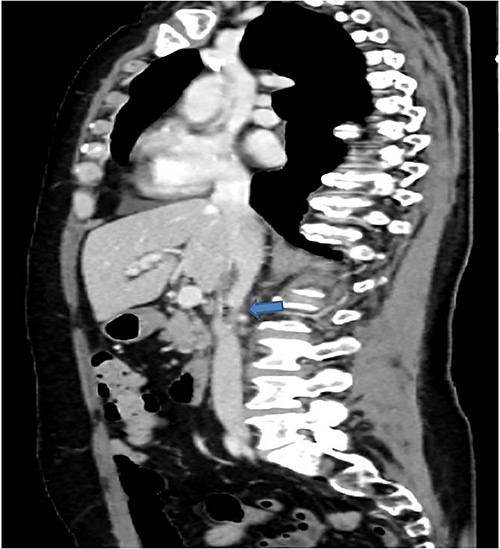

Therefore, given the persistence of the septic state and the radiological findings, the patient underwent laparotomy. Dense retroperitoneal fibrosis surrounded the IVC and the third section of the duodenum (Fig. 3). After complete mobilization of the duodenum with exposure and preparation of the entire subhepatic inferior caval vein and the two renal veins, the duodenal incision located at the level of the posterior wall of its third portion and the caval vein were sutured (Fig. 4). The cholecystectomy with Kehr drainage placement to protect the bowel suture and a jejunostomy were performed.

The complete kocherization of the duodenum (1) allowed to better identify the site of the fistula (2) and of the caval thrombus (3) allowing an adequate control of the left renal vein (4).